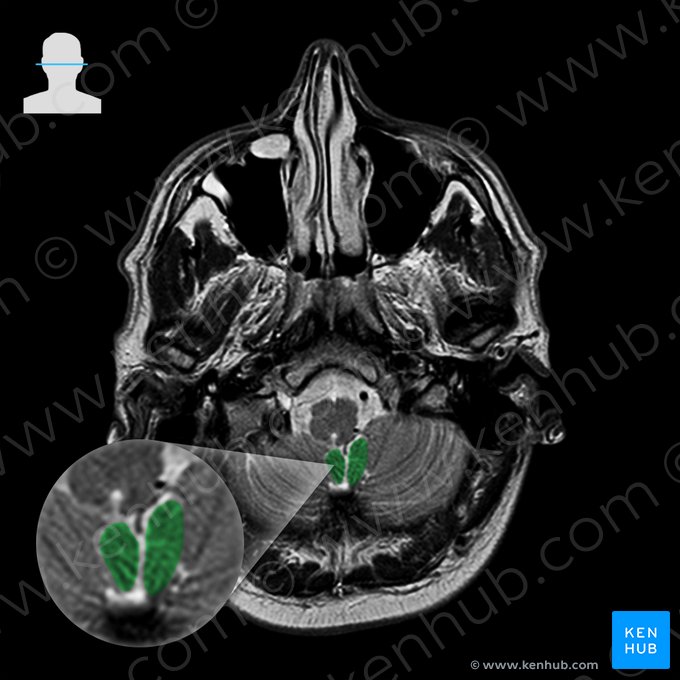

One of the most important sequences for brain imaging is one called T2-weighted sequence. On T2-weighted images cerebrospinal fluid (CSF) - or any type of clear fluid - shows a marked hyperintensity (white color), while still allows for a fair differentiation between the gray and white matter of the brain.

The following images will show you some of the anatomical structures that are identifiable with T2-weighted MRI of the brain.